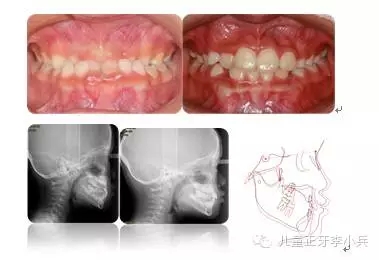

1. 兒童牙病的治療與錯(cuò)合畸形的預(yù)防:兒童齲病造成牙冠橫徑變短、乳牙早失、磨牙前移。兒童根尖周病影響恒牙發(fā)育及萌出異常,阻生。兒童牙病治療、間隙維持能預(yù)防繼承恒牙的萌出異常。(圖2,病例一)

40.webp.jpg

圖2 75深齲,34牙胚萌出異常,拔出75,舌弓間隙維持后,34萌出道自行調(diào)整萌出;